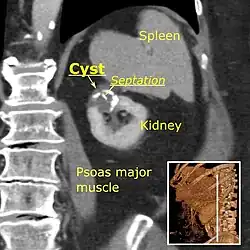

-

Renal ultrasonography of a simple renal cyst with posterior enhancement. -

Bosniak II cyst at the lower pole of right kidney with septations within.